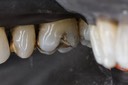

Ted Kanamori #12-14 finish